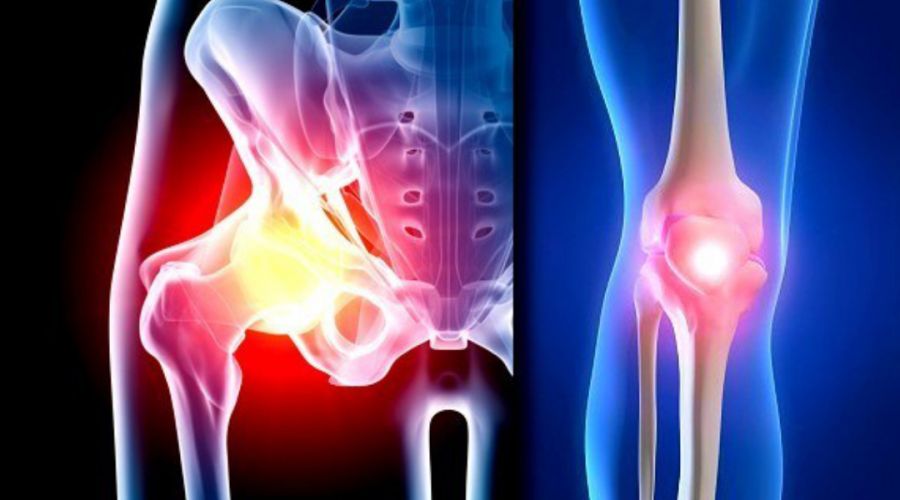

Diz ve kalçalarınızda kireçlenme var mı?

Prof. Dr. Azboy, günümüzde yaşlı nüfusun artmasına paralel olarak diz ve kalça kireçlenmelerinde ciddi artış görüldüğünü belirterek, 'Buna bağlı olarak diz ve kalça protezi ameliyatları her geçen gün daha yüksek sayılarda uygulanmaktadır. Diz ve kalça eklem protezleri hastaların yaşam kalitelerine ciddi anlamda katkı sunan başarılı ameliyatlardır.

Prof. Dr. Azboy, günümüzde yaşlı nüfusun artmasına paralel olarak diz ve kalça kireçlenmelerinde ciddi artış görüldüğünü belirterek, 'Buna bağlı olarak diz ve kalça protezi ameliyatları her geçen gün daha yüksek sayılarda uygulanmaktadır. Diz ve kalça eklem protezleri hastaların yaşam kalitelerine ciddi anlamda katkı sunan başarılı ameliyatlardır.